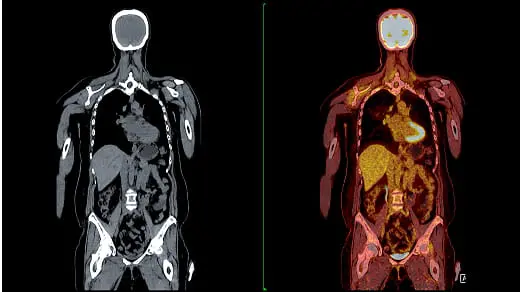

全身MRI または PET/CT

• 全身MRI:8~12万

• PET/CT:7~15万

• 胸部CT:2~4万

• 頭部MRI:3~7万

• 胃内視鏡:1.5~4万

• 大腸内視鏡:2~6万

Q 他の検査(PET/CTやMRI)との違いは何ですか?

A PET/CTやMRIは、苦手ながんやカバーされない部位があります。また、腫瘍部分が1cm程度の大きさにならないと発見できません。その点 マイクロCTC検査は全身のがんリスクを一度の検査で判明でき、腫瘍が1cm以内の大きさでも、間葉系のがん細胞に悪性化したものは検 出することが可能です。